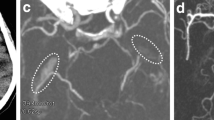

Patients were included if they met the following criteria: (1) occlusion of the ICA, (2) no high-grade contralateral ICA stenosis, (3) sufficient pretreatment computed tomography perfusion (e.g., good opacification, low movement artifacts) and patent distal cerebrovascular arteries as detected by CTA (especially no tandem-occlusions) and (4) available information on the underlying etiology. A structured, interdisciplinary procedure was employed to determine the etiology of carotid occlusion in accordance with current guidelines. Clinical information, including neurological symptoms and medical history, was supplemented by findings from imaging modalities such as CT-A, digital subtraction angiography (DSA), and color-coded duplex sonography. A cardiologic assessment was conducted to investigate any potential sources of thrombus, incorporating echocardiography, duplex ultrasounds, 24‑h Holter electrocardiography, and relevant laboratory diagnostics. The diagnosis of the precise etiology of the stroke was established through a combination of these clinical tests and imaging observations, such as those obtained during endovascular treatment (e.g., occluded macroangiopathic stenosis, visible dissection, or thrombus occlusion without underlying carotid pathology). Additionally, the Trial of Org 10172 in Acute Stroke Treatment (TOAST) criteria were applied in the diagnostic process [14]: (1) for a macroangiopathic occlusion, calcifications of the carotid artery must be present, which can lead to typical changes, e.g., by Doppler and color-coded duplex ultrasound, and at the same time, neurological symptoms must not be reasonably explained by another cause; (2) for an embolic occlusion, a confirmed source of embolism must be present, without, e.g., extensive arteriosclerosis; (3) for a dissection, a source of embolism and extensive arteriosclerosis must be excluded and typical morphological criteria, e.g., in DSA, magnetic resonance imaging or CT‑A (i.e., string sign or intramural hematoma), must be fulfilled [10]. Typical occlusion patterns may be seen in CT‑A or DSA with higher sensitivity of the latter (Fig. 1; [15]). Only patients in whom the etiology could be determined with reasonable certainty were included. Patients included are those who received intravenous thrombolysis (IVT), endovascular thrombectomy (ET), a combination of both therapeutic options and no therapy (Table 1).

Angiographic images of different etiologies of internal carotid artery (ICA) occlusions. Angiographic images in lateral projection of (a) a dissection of the ICA with vessel wall irregularities and string sign (arrowhead), b a thromboembolic occlusion of the ICA and distal common carotid artery with a sudden, irregularly bordered filling defect, c a macroangiopathic occlusion of the ICA with an hourglass-shaped, irregularly bordered tapering of the vessel and sudden filling defect (open arrow); Contrast agent was administered via 8F arrow sheath in these examinations

The underlying etiology of an ICA occlusion is an important factor for the acute treatment of the patient and a prognostic factor for patient outcome [3, 5, 16, 17]. Angiographic imaging may be helpful in determination of the underlying etiology of the ICA occlusion, but noninvasive, pretreatment determination is desirable [18]. In this context, it is useful to evaluate CTA, in which the visualization of the occlusion is very accurate, but the filling defect cannot be imaged as sensitively as in DSA, which may complicate inference of the underlying etiology [19]. Besides imaging of the occlusion itself, the age of patients allows a reference to the cause of ICA occlusion: young patients suffer more frequently from dissection and patients with an older age more frequently show macroangiopathic or embolic ICA occlusions, which is in line with the findings in our current study [10]. Furthermore, some preconditions are suggestive for a specific etiology as atrial fibrillation is common in patients with embolic occlusions and dissections are slightly more frequently found in male patients [20]. We were able to observe these coherences in our study sample as well and could show that there are markedly distinguishable age differences between each of the three etiologies evaluated.